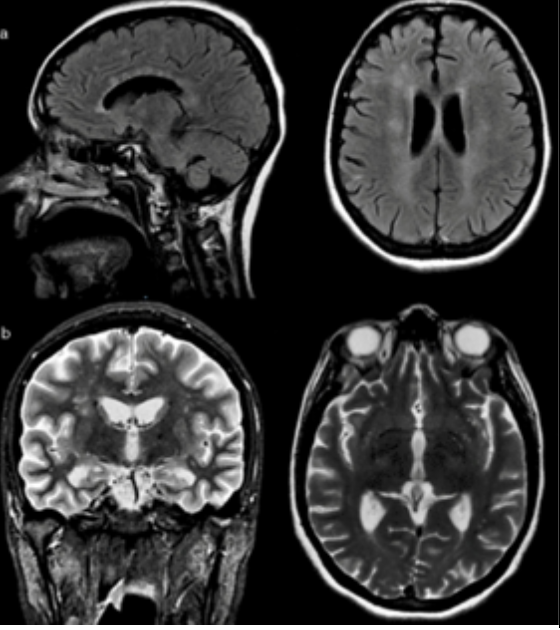

Observe and analyze the image of the brain obtained by MRI and answer the questions:

Analyze the MRI image with the diagram and what you have learned in class, trying to identify and compare its parts. To do this you can be guided by questions 2-4:

2. We see four images of a skull, identify which one is taken in profile, which one from the top, which one from the back and which one from the bottom of the skull.

3. Identify in the a-izq image the cerebrum, cerebellum and brainstem.

4. Say which structures we observe in light color at the end of the image b-right.